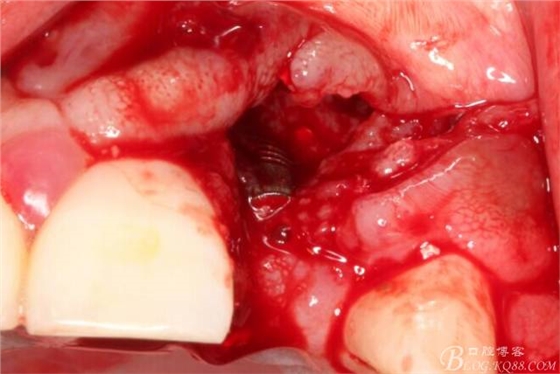

于是我果斷告知患者,手術(shù)失敗了,不能拖延,如不及時處理,炎癥繼續(xù)發(fā)展會很快波及鄰牙牙槽骨。患者接受我的建議。切開翻瓣,骨粉及生物膜消失了,骨吸收嚴(yán)重,幸運的是,因為處理及時,鄰牙骨支持依然存在。

徹底掻刮。